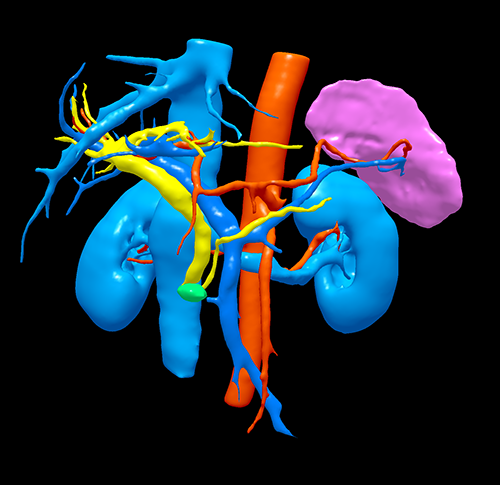

胰头腺癌---胰十二指肠切除